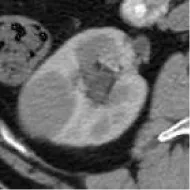

Patients with a pathological diagnosis obtained by biopsy or surgical resection were included in this study. In addition, 80 patients with available arterial/cortical/nephrogenic phase CT image sequences were reviewed (42 with PRCC and 38 with ChRCC). After randomly selecting 6 cases (3 PRCCs and 3 ChRCCs) for testing sets, the images of 74 tumors (39 PRCCs and 35 ChRCCs) were used to build the datasets. The CT images were obtained using various radiology scanners and non-standard protocols. Arterial phase sequences were preferred when multiple phases existed. Whole sequences were retrieved and exported utilizing the hospital radiological database. The window settings were 40 HU (width) and 400 HU (level). Based on the clinical and pathological data, ROIs of sequences were segmented, labeled, and exported with ITK-SNAP by two abdominal radiologists who have experience of more than 10 years in the diagnosis of urinary system tumor. After cross-validation, images that were exported in.jpg size included 857 images of ChRCCs and 997 images of PRCCs. Labeling was applied in the non-graphical layer so that each slice filename contained the case number, gender, age, and histological subtypes. After resizing, images comprised matrices with 256 * 256 pixels in the axial planes. The dataset was divided into the training set and validation set (90% for the training set and 10% for the validation set).